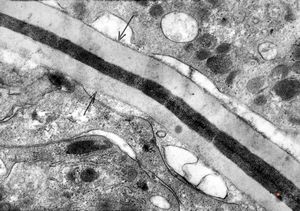

M,18y. | blood - tubular inclusions in lymphocytes